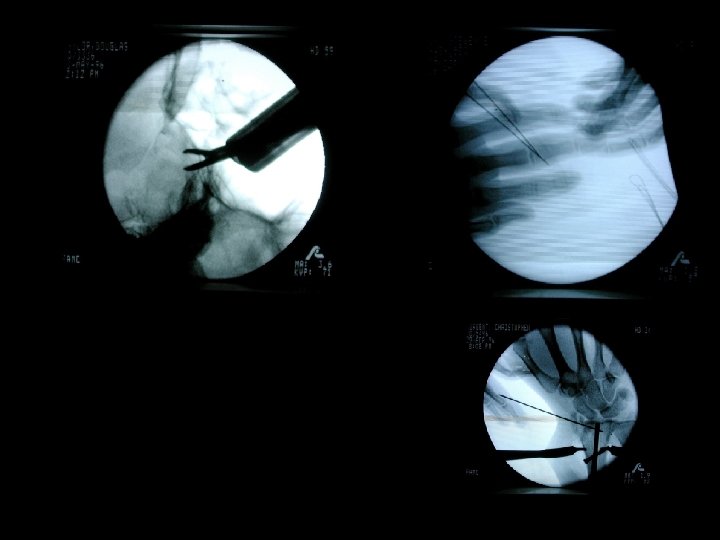

FLUOROSCOPY IMAGES IN MOTION

FLUOROSCOPY EQUIPMENT